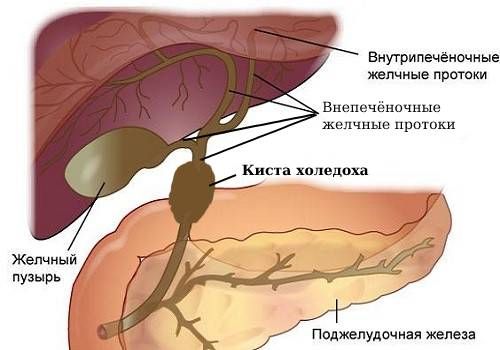

Анатомия и особенности Гартманова кармана желчного пузыря